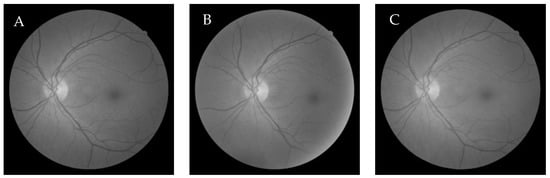

6.3. Comparative Study of the GWO-Based Different Demons Registration